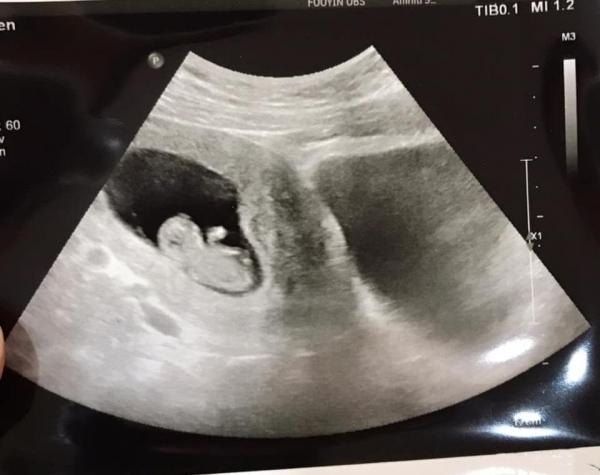

就在進行一連串的儀式後,媽祖娘娘透露馬上就會有好消息,還準備的中藥方、求子符令跟一朵花,結果就在今年,他們真的做人成功,讓她感謝神明、小女孩的成全:「有神則靈,保持慈悲心態,必有奇蹟!」